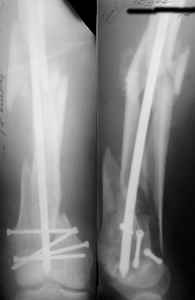

I presented a series of ~25 such cases at EuroTrauma'2004. Many cases were discussed here. I attach am example. Look also recent cases at http://www.hwbf.org/hwb/conf/alex58/scfx.htm,

http://www.hwbf.org/hwb/conf/alex63/alex63.htm

Did you mark valgus malalignment in that case with LISS you posted Nov 9? Aplication of external distractor can help to avoid the pitfalls but some further development of the technology is necessary to shorten the learning curve.

- Your last posted case: how is possible to have secure fixation with applied construct without additional casting, bracing or Ilizarov?

THX, initial images are

1,

2.

At that moment we had in stock only the 10 mm solid nails so of course there was no idea about early weight bearing. But it was quite enough for early knee ROM excersises (see attached). Two locking screws through the distal block provided that.